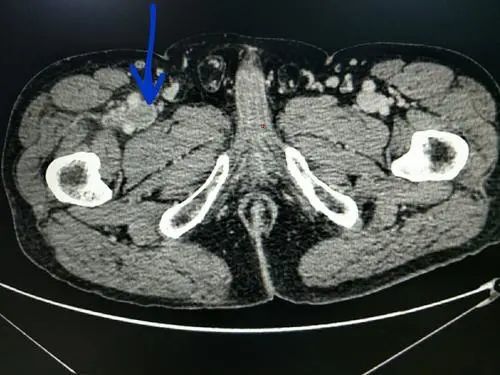

后来去医院一检查,结果竟然是:

大腿和手臂等多处血管,出现了血栓!